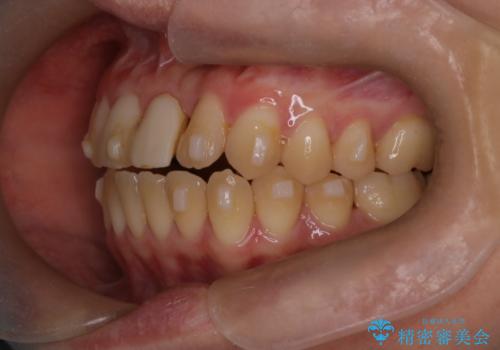

前歯の開咬とシザーズバイトを改善|インビザライン矯正

- 治療計画

前歯が噛まないため咀嚼が困難で、シザーズバイトにより噛み合わせに不調を感じていました。インビザラインを用いて、透明なマウスピースによる目立ちにくい矯正治療を実施。奥歯のシザーズバイトを改善した後、前歯の歯列を緻密に調整し、噛み合わせを整えました。定期的なマウスピース交換を通じて徐々に歯列が改善され、治療終了後には前歯が正常に咬合するようになり、噛み合わせの機能性と審美性が共に向上しました。